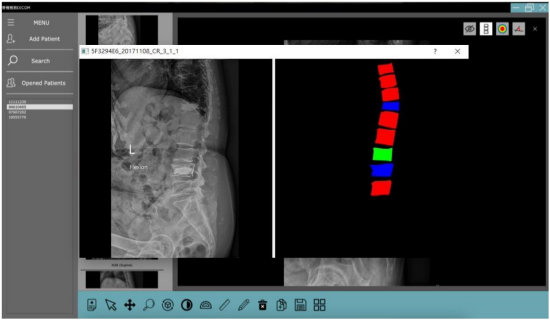

本研究主要探討椎體成形術後發生鄰近節椎體續發性骨折的分析及其預測,將建構一個預測模型,從X光影像處理、椎骨分割與計算角度與曲度等,推算出各節鄰近椎體間發生續發性骨折的機率並以類似熱區圖的方式呈現,並且設計一套圖形化人機互動介面(Graphical User Interface,GUI),除了以上功能之外希望能結合病患的相關院內資料,讓醫護人員能更方便操作與查看。希望不僅能幫助預測併發症的發生並加以預防,也能減輕人力資源在影像判讀上的消耗。